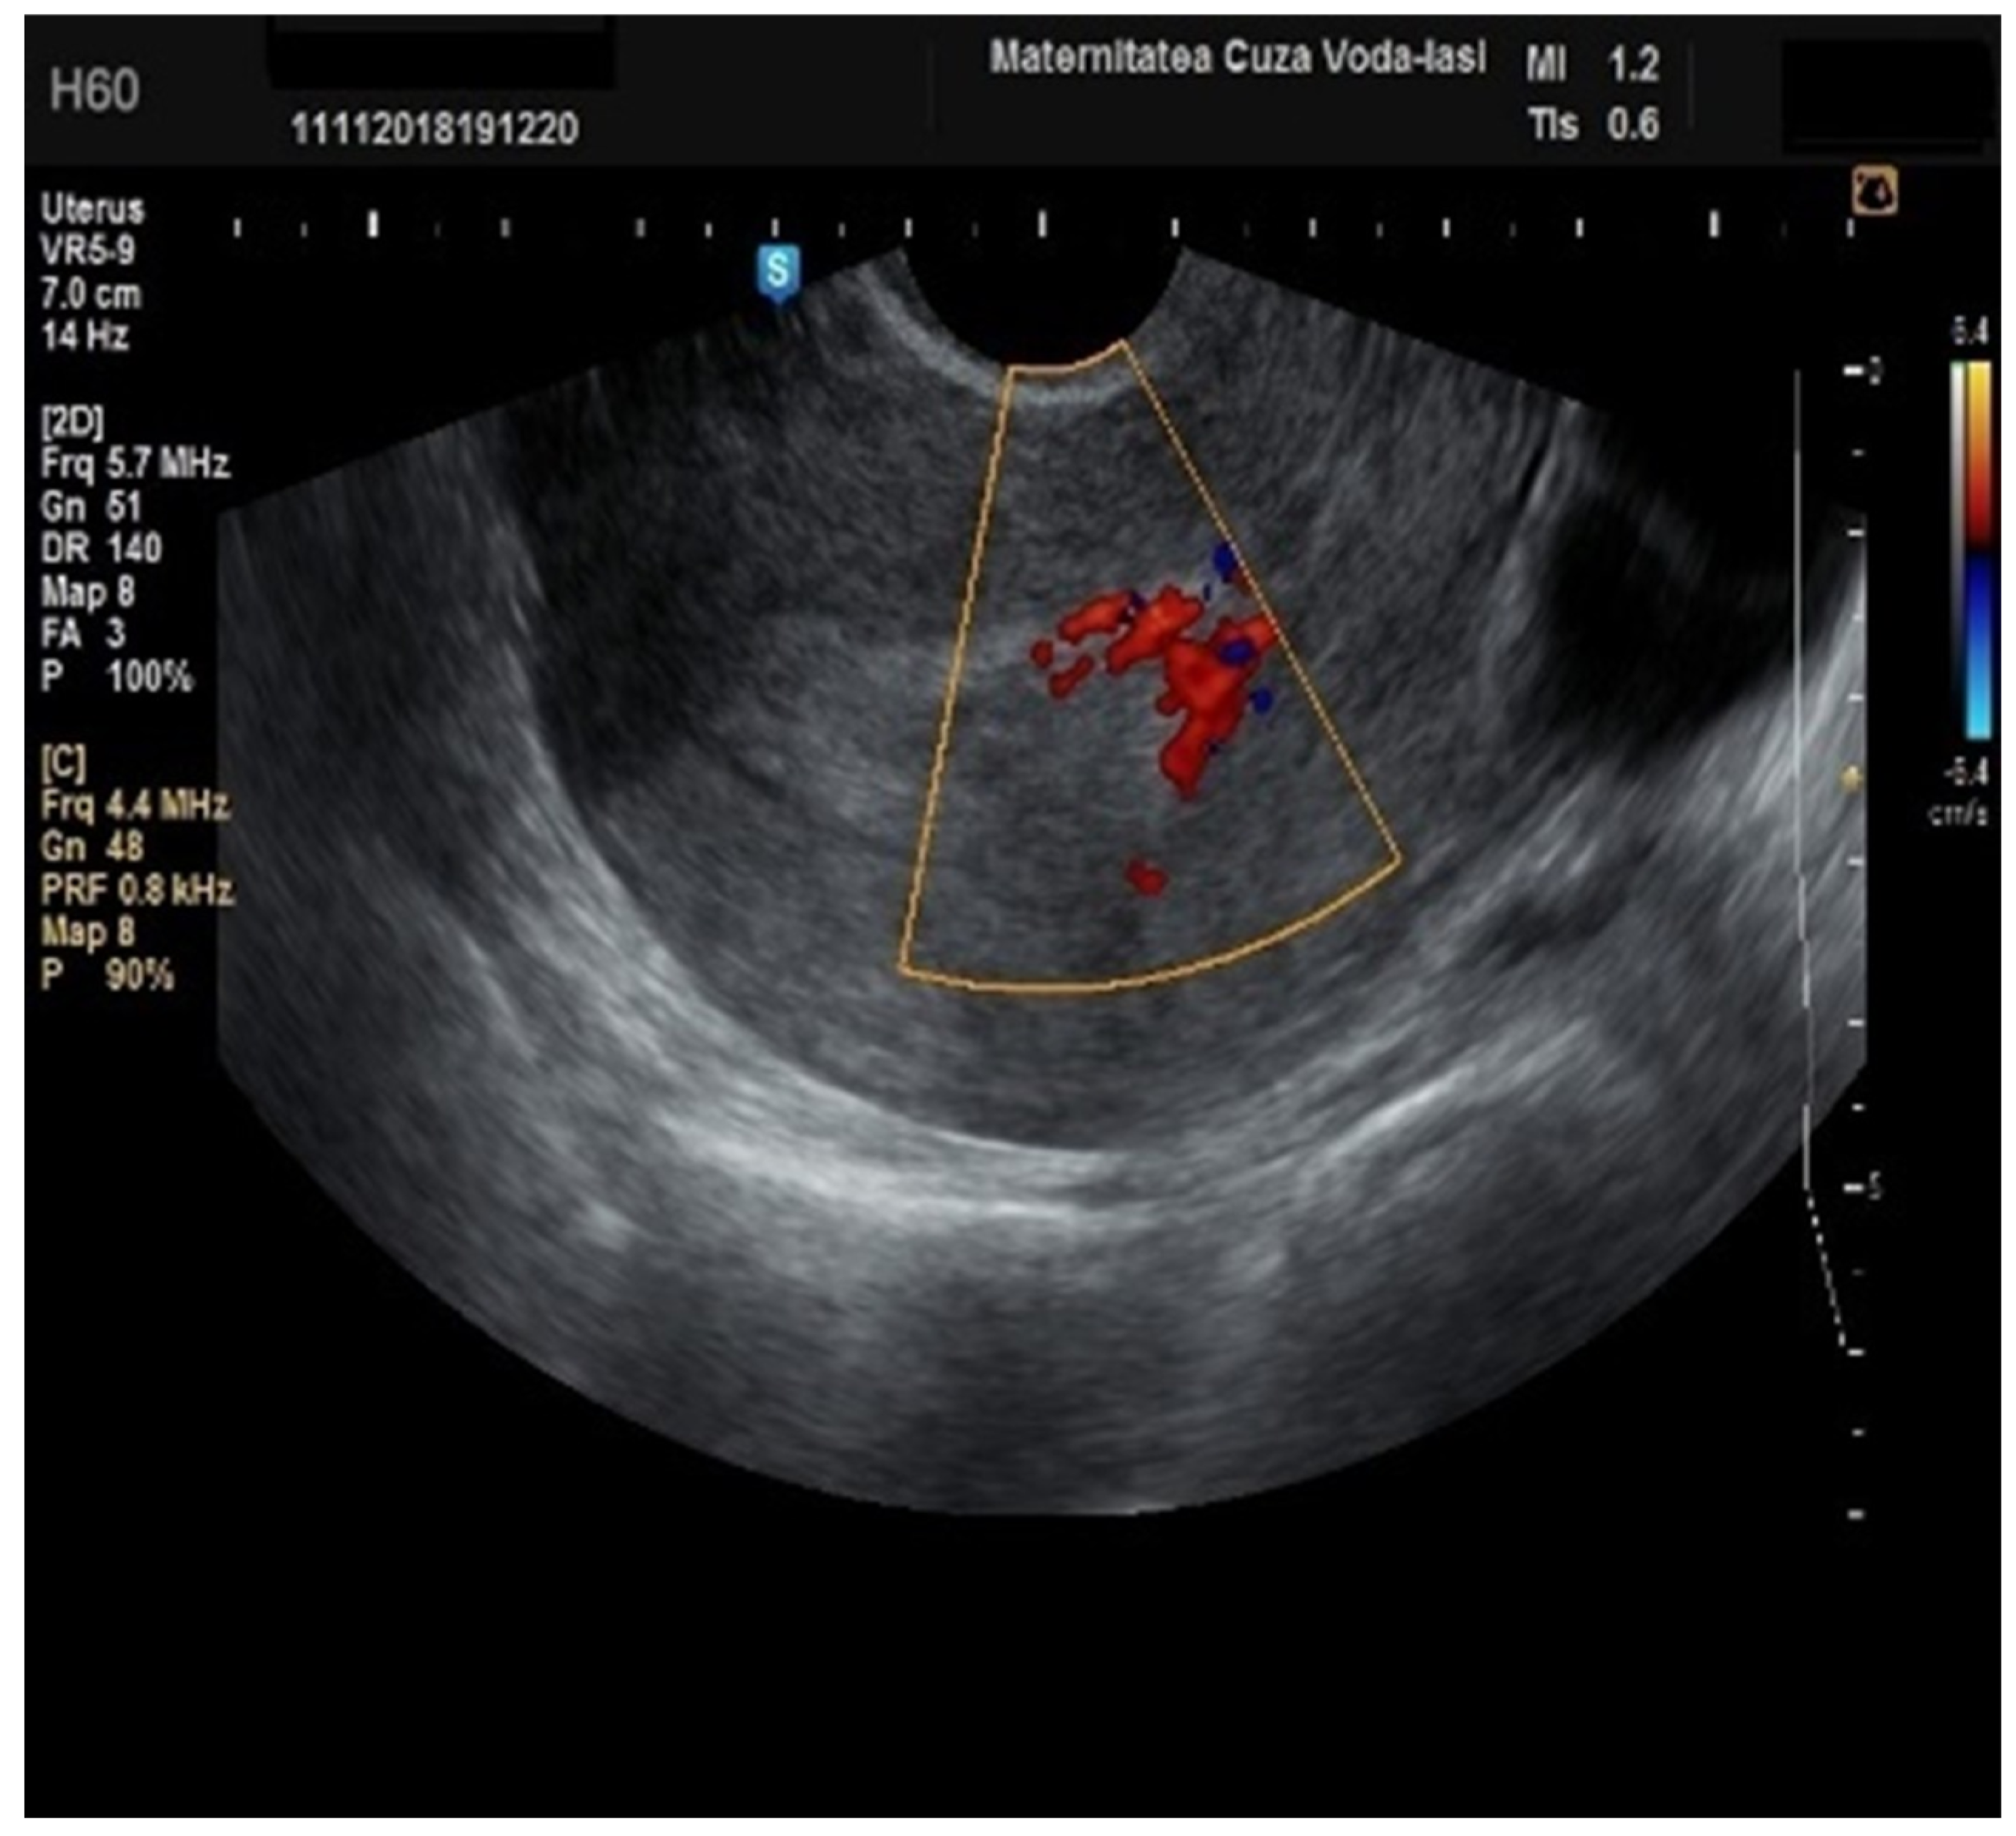

Regarding the color Doppler assessment, a vascular score of 1 usually excludes endometrial cancer, with a sensitivity of 87.5% and a specificity of 79% (Figure 8). This is due to the presence of a high number of newly formed vessels in malignant tumors (Figure 9).

Furthermore, color Doppler imaging proved valuable in more accurately determining myometrial invasion. The predominant feature of blood vessels in endometrial cancer was the presence of scattered vessels (Figure 10), which demonstrated a sensitivity of 50% (95% CI: 0.2152 to 0.7848) and a specificity of 94.74% (95% CI: 0.8563 to 0.9819). Additional vascular aspects indicative of endometrial cancer were the presence of vessels with various branches (Figure 11) and color splashes (Figure 12).

Figure 9. Color Doppler vascular score 4 in endometrial cancer.